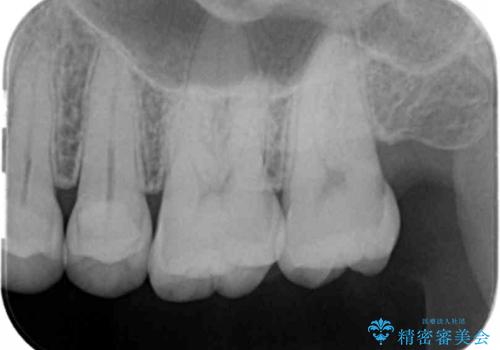

- 検査の結果、左上の一番奥の歯のさらに奥の面の深い位置に虫歯が潜んでいることを確認しました。

外から見えない位置であるため、セラミックよりも精度を上げることができるゴールド(PGAインレー)で修復していきます。

昔親知らずが埋まっていた場所にできてしまった虫歯であるためかなり深い位置に潜り込むような虫歯でした。

このような虫歯でも丁寧に処置することで問題なく適合の良いインレーを入れることができます。